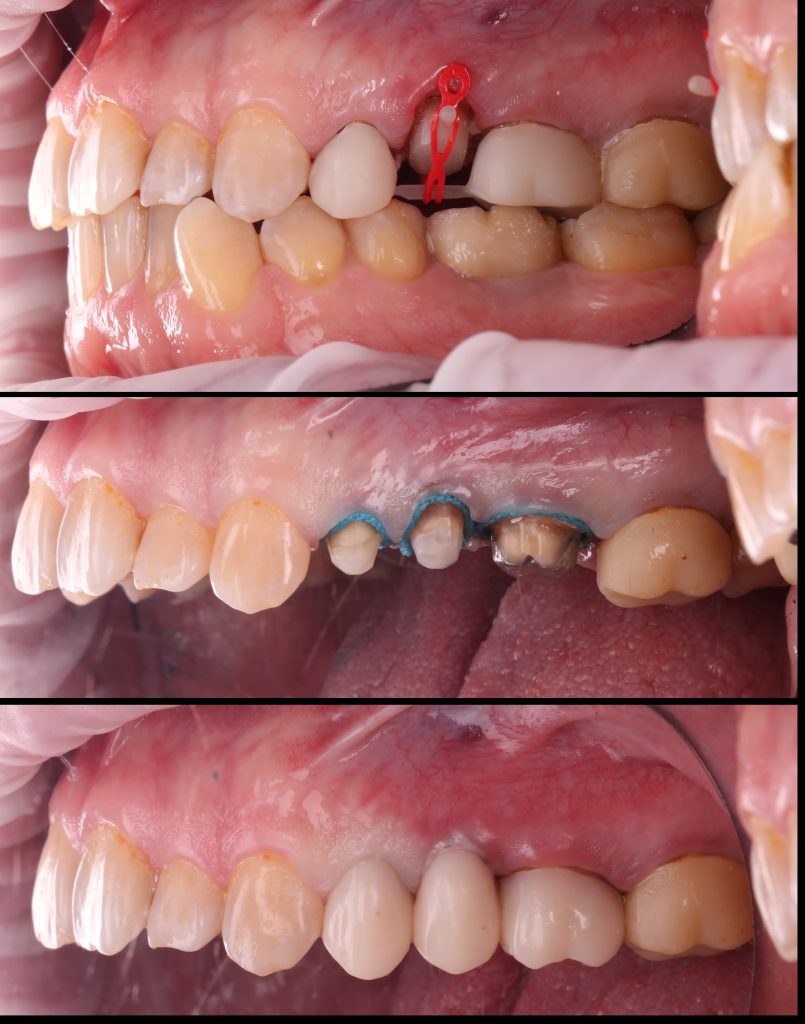

Wir stellen einen Fall einer Zahnextraktion 15 (Universal 4) vor, bei dem eine kieferorthopädische Konstruktion verwendet wurde, um die Höhe der klinischen Krone zu erhöhen. Dadurch konnte der Zahn erhalten und die prothetische Behandlung fortgesetzt werden.

Der Patient stellte sich mit Beschwerden über die Beweglichkeit der Brücke an den Zähnen 14 (Universal 5) und 15 (Universal) vor.

Es wurde genügend Hartgewebe über der Gingiva gewonnen, um einen Ferrule-Effekt zu erzielen. Die erste Phase der prothetischen Rehabilitation wurde mit dem Einsetzen der provisorischen Kronen abgeschlossen.